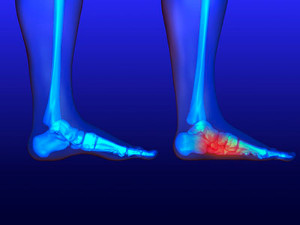

The sesamoids are two small, pea-shaped bones found just under the base of the big toe. The sesamoids are embedded in a tendon, allowing you to move the big toes and acting as shock absorbers in the foot while you walk and run. Though these bones are quite small, they can be easily injured. The area around the sesamoid bones may become inflamed due to injury or overuse, leading to sesamoiditis. Over time, these bones may become unable to bear the load placed on them and could even develop tiny stress fractures. A sudden injury to the bones can cause them to fully fracture. If you have pain, swelling, or bruising in the ball of your foot, schedule an appointment with a podiatrist who can diagnose and treat various sesamoid injuries.

Sesamoiditis is a condition of the foot that affects the ball of the foot. It is more common in younger people than it is in older people. It can also occur with people who have begun a new exercise program, since their bodies are adjusting to the new physical regimen. Pain may also be caused by the inflammation of tendons surrounding the bones. It is important to seek treatment in its early stages because if you ignore the pain, this condition can lead to more serious problems such as severe irritation and bone fractures.

The cause of sesamoiditis is sudden increase in activity. The ball of your foot acts as a springboard to help you lift off when you are jogging or running. Sudden increase in the use of these bones or the tendon that controls them can cause irritation. The tendon then begins to develop inflammation and the joint begins to swell. People with smaller, bonier feet or those with a high arch are typically more susceptible to this condition.